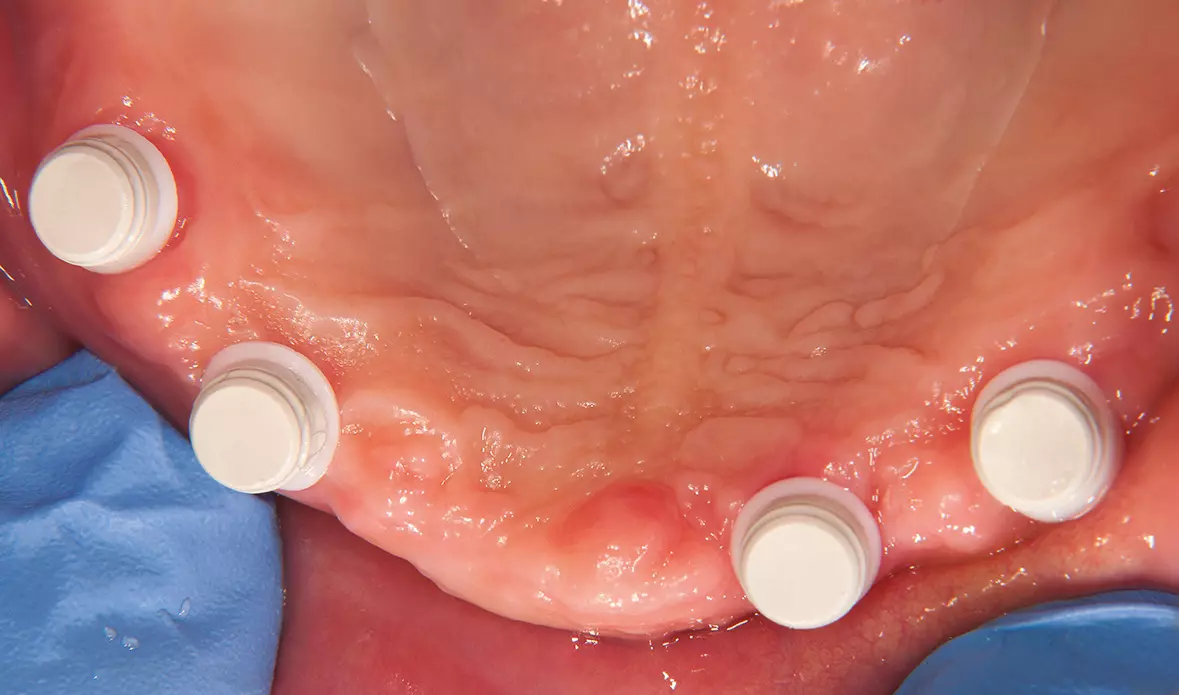

Abb. 19: Nach drei Monaten Einheilzeit, Entnahme der Healing Caps und Aufsetzen der Abdruckpfosten. Dr. Michael Leistner

Abb. 19: Nach drei Monaten Einheilzeit, Entnahme der Healing Caps und Aufsetzen der Abdruckpfosten.